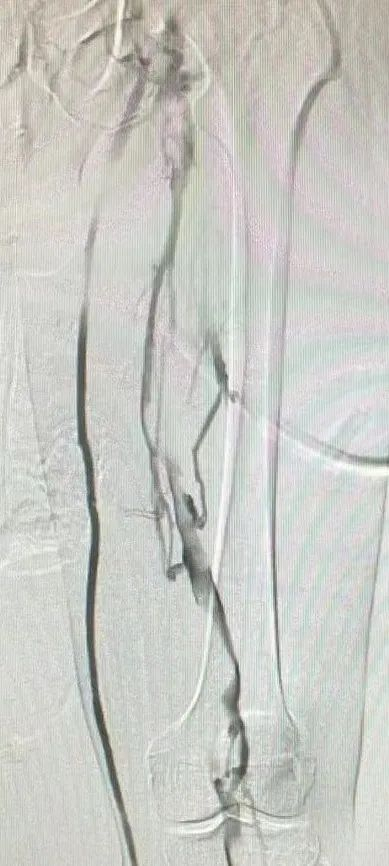

患者取仰卧位,在局部麻醉下通过左侧足背静脉顺行造影,结果显示左侧髂股静脉血栓负荷较重。随后,经右侧股静脉入路,成功置入血栓保护装置于下腔静脉预期位置,确保术中脱落的血栓能够被有效拦截。之后,再经左侧腘静脉入路,对髂股静脉狭窄区域依次进行血栓清除术和球囊扩张术,并成功植入髂静脉支架。术后造影显示,左侧髂股静脉血流恢复通畅,同时血栓保护装置内见少量血栓充盈缺损,随后经右侧股静脉负载血栓回收血栓保护装置,并将其撤出体外,取出后可见拦截到的不同尺寸的血栓,手术顺利完成。

造影血栓保护装置

拦截到血栓